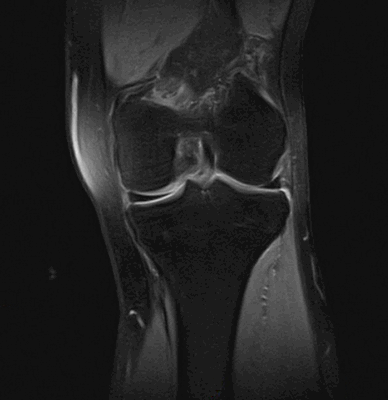

На МРТ хорошо прослеживаются все стадии этого процесса. На томограмме определяется выпот синовиальной жидкости и подхрящевая костная киста при остеоартрозе коленного сустава.

Сначала появляется неровность поверхности хряща, так как он теряет свою упругость и эластичность. Далее он становится менее компактным, разделяется на отдельные волокна, обнажая участок подлежащей кости. От хряща могут отделяться фрагменты, которые попадают внутрь сустава, это явление называют «суставные мыши». В случае их попадания и сдавления между суставными поверхностями у человека возникает внезапная острая боль. При каком-то определенном смещении в колене «суставная мышь» изменяет своё положение и боль заканчивается так же внезапно, как началась.

Фронтальный срез МРТ коленного сустава